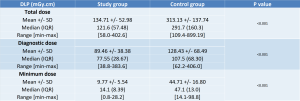

The Dose Length Product (DLP) in the study group was significantly lower than in the control group (Table 2; Figure 1).

The study group had a mean total DLP of 134.71 mGy.cm, compared to 313.13 mGy.cm in the control group. This equates to a dosage reduction of 56.97%.

The mean DLP for diagnostic acquisitions was 89.46 mGy.cm in the study group against 128.43 mGy.cm in the control group. This equates to a dosage reduction of 30.34%.

The mean DLP for minimal dose acquisitions was 9.77 mGy.cm in the study group against 44.71 mGy.cm in the control group. This equates to a dosage reduction of 78.4%.